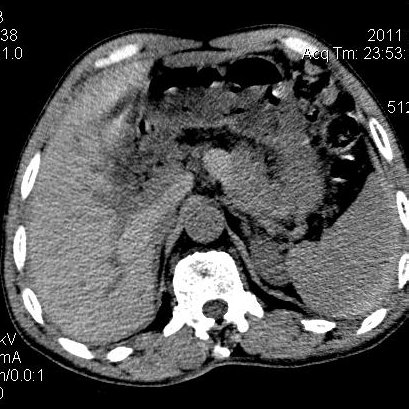

肝左叶发育异常

男性,55岁,骑摩托车摔倒后入院,自述右上腹疼痛

[backcolor=#FF0000]第一次诊断的时候也是这么肯定,可是床旁超声检查并没有发现明显异常,而且患者的一般症状都良好。还好临床只是保守治疗,没有立即手术,第二次复查的时候没有一点变化,又做了MRI检查,没有血肿,

这是一例肝左叶发育异常的,很个性吧~[/backcolor]